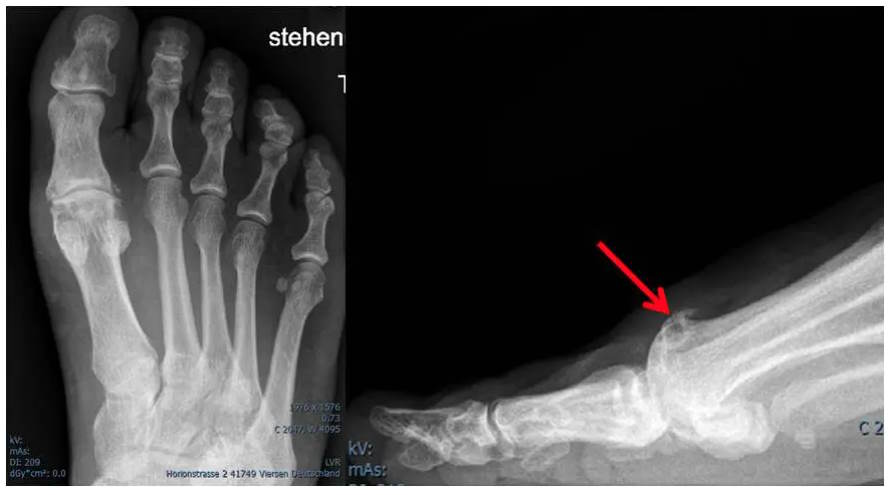

Bildgebende Diagnostik

Ein Röntgenbild im Stand in dorso-plantarer (d.p.) und streng seitlicher Ausrichtung zeigt die typischen Arthrosezeichen des Großzehengrundgelenkes:

- Gelenkspaltverschmälerung

- subchondrale Sklerosierung

- Exophyten

- Deformierung des Gelenkes

welche stadienabhängig unterschiedlich stark ausgeprägt sind.

Der Hallux rigidus lässt sich grob in drei Stadien unterteilen:

- Stadium I: geringe-mäßige Schmerzen, leichte bis mäßige Einschränkung der Bewegung, beginnende radiologische Veränderungen im Sinne einer Arthrose.

- Stadium II: intermittierender Ruheschmerz, starke Bewegungseinschränkung, deutliche radiologische Veränderungen im Sinne einer Arthrose

- Stadium III: starke Schmerzen, komplette Einigung des Gelenkspaltes mit Ausbildung überbrückender Osteophyten